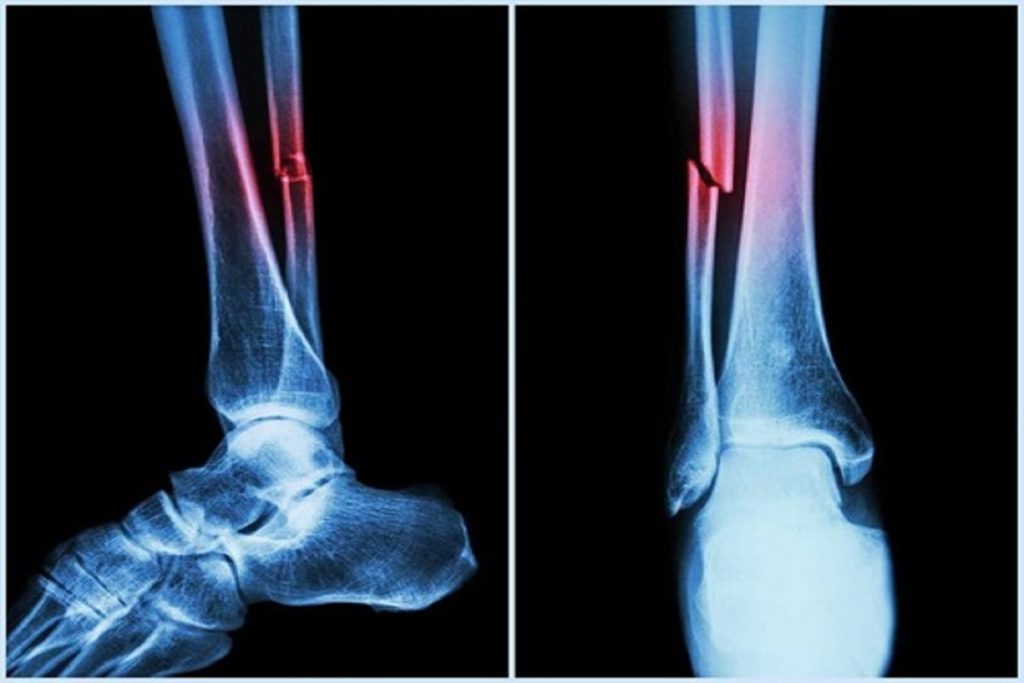

एक और रिसर्चर मार्क सिम ने पाया कि एएसी न सिर्फ दिल की बीमारी का संकेत है, बल्कि यह गिरने और हड्डी टूटने का भी बड़ा कारण हो सकता है। उन्होंने कहा कि नया एल्गोरिदम पुराने तरीकों से ज्यादा सही जानकारी देता है।

उन्होंने कहा, “हमने पाया है कि जितना अधिक एएसी होता है, व्यक्ति के गिरने और हड्डी टूटने का खतरा उतना ही ज्यादा होता है। डॉक्टर आमतौर पर इस पर ध्यान नहीं देते, लेकिन यह नई तकनीक इस कमी को पूरा करती है।”

नतीजा यह है कि अब हड्डियों की जांच के दौरान ही मरीज की धमनी और दिल की सेहत की भी जानकारी मिल सकती है, जिससे हड्डी कमजोर होने पर गिरने के जोखिम या फ्रैक्चर का पहले ही पता लगाकर समय रहते इलाज किया जा सकता है।